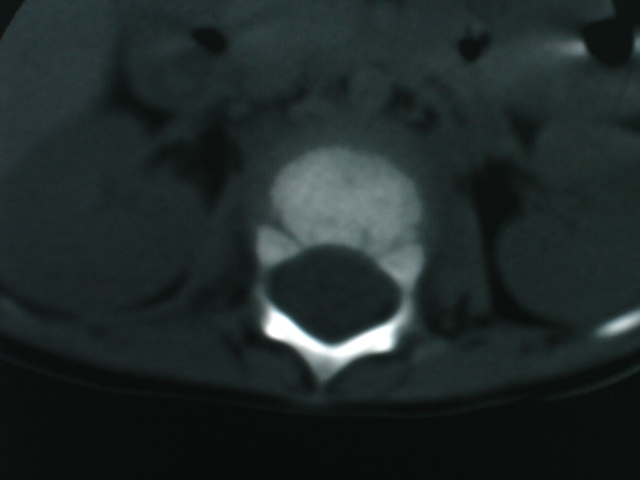

椎体周围见类软组织密度影,椎体见虫蚀样破坏,考虑tb.性。

椎体骨质破坏,椎体周围见软组织密度影.椎体结核

椎体破坏明显,周围软组织肿胀,椎间盘未见明显受累.结核

椎体破坏明显,周围软组织肿胀,椎间盘未见明显受累.考虑结核

椎体结核合并冷脓肿形成。

椎体破坏明显,周围软组织肿胀,椎间盘未见明显受累.考虑椎体结核合并冷脓肿形成。

体破坏明显,周围软组织肿胀,椎间盘未见明显受累.考虑椎体结核合并冷脓肿形成.注意排除嗜酸性肉芽肿